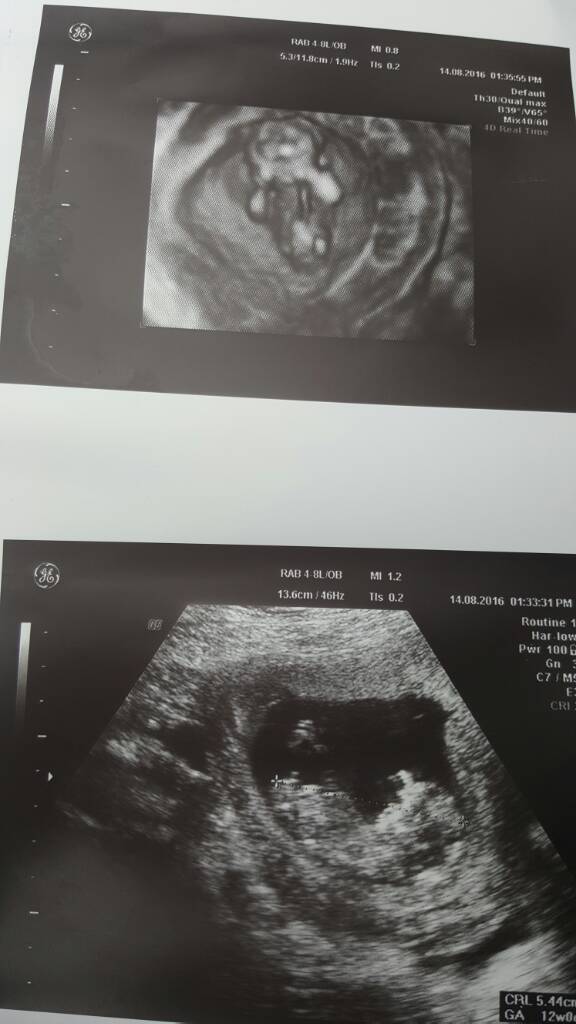

U mnie wszystko w najlepszym porządku. Lekarz nawet stwierdził że może być chłopak bo coś tam wystaje [emoji12] zrobił nawet 4d i wszystko dobrze. Najgorsze za nami [emoji4] przez mdłości i wymioty schudłam 6 kg. Zobacz załącznik 767619

Zobacz załącznik 767620